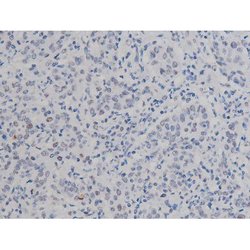

Antibody detects endogenous levels of Nucleophosmin only when phosphorylated at Threonine 199.

| Applications | Immunohistochemistry (Paraffin), Western Blot, Immunocytochemistry |